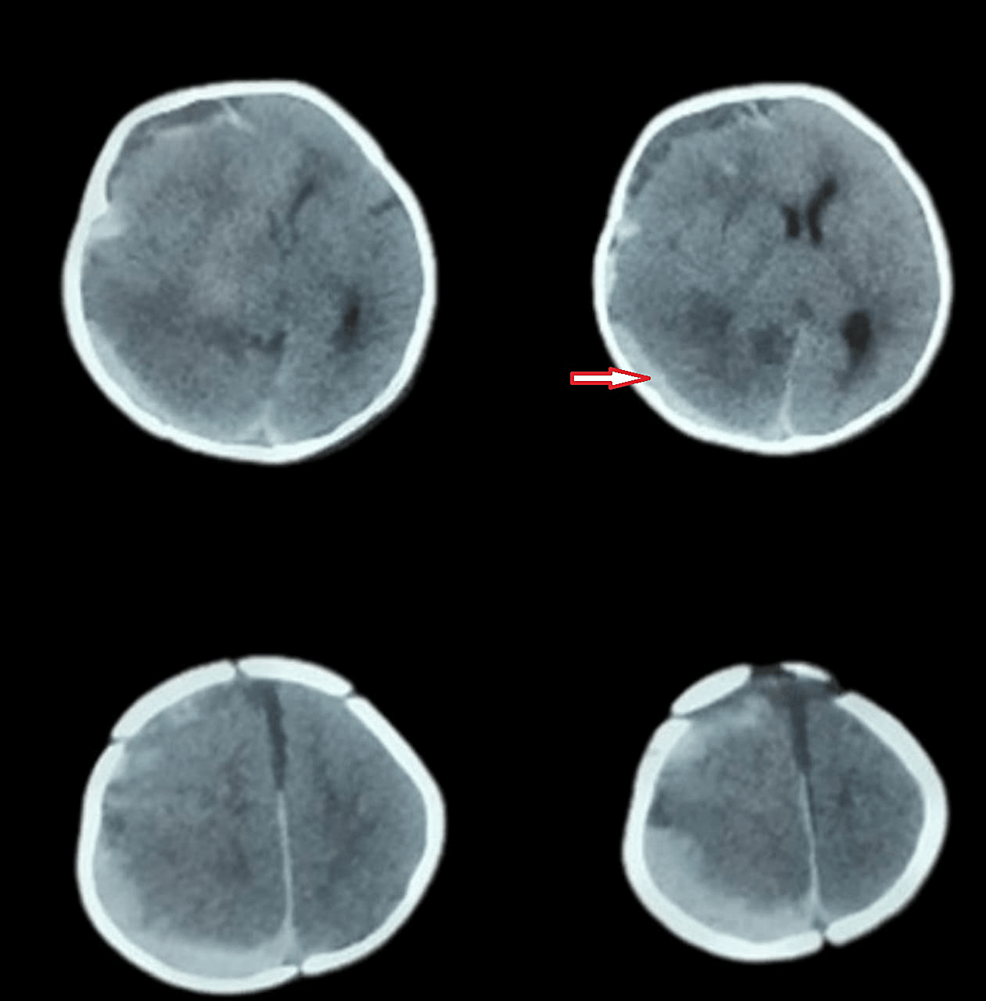

AcuteonChronic Subdural Hemorrhage Due to Late Vitamin K Deficiency Late Vitamin K Deficiency Bleeding In general, infants with vitamin k deficiency bleeding (vkdb) do not require surgical care, but in rare cases, an infant may need. In this study, clinical and demographic features of 16 cases with late vitamin k deficiency bleeding are presented. Late vkdb is often linked to malabsorption secondary to liver disease and poor intake of vitamin k. Infants who do. Late Vitamin K Deficiency Bleeding.